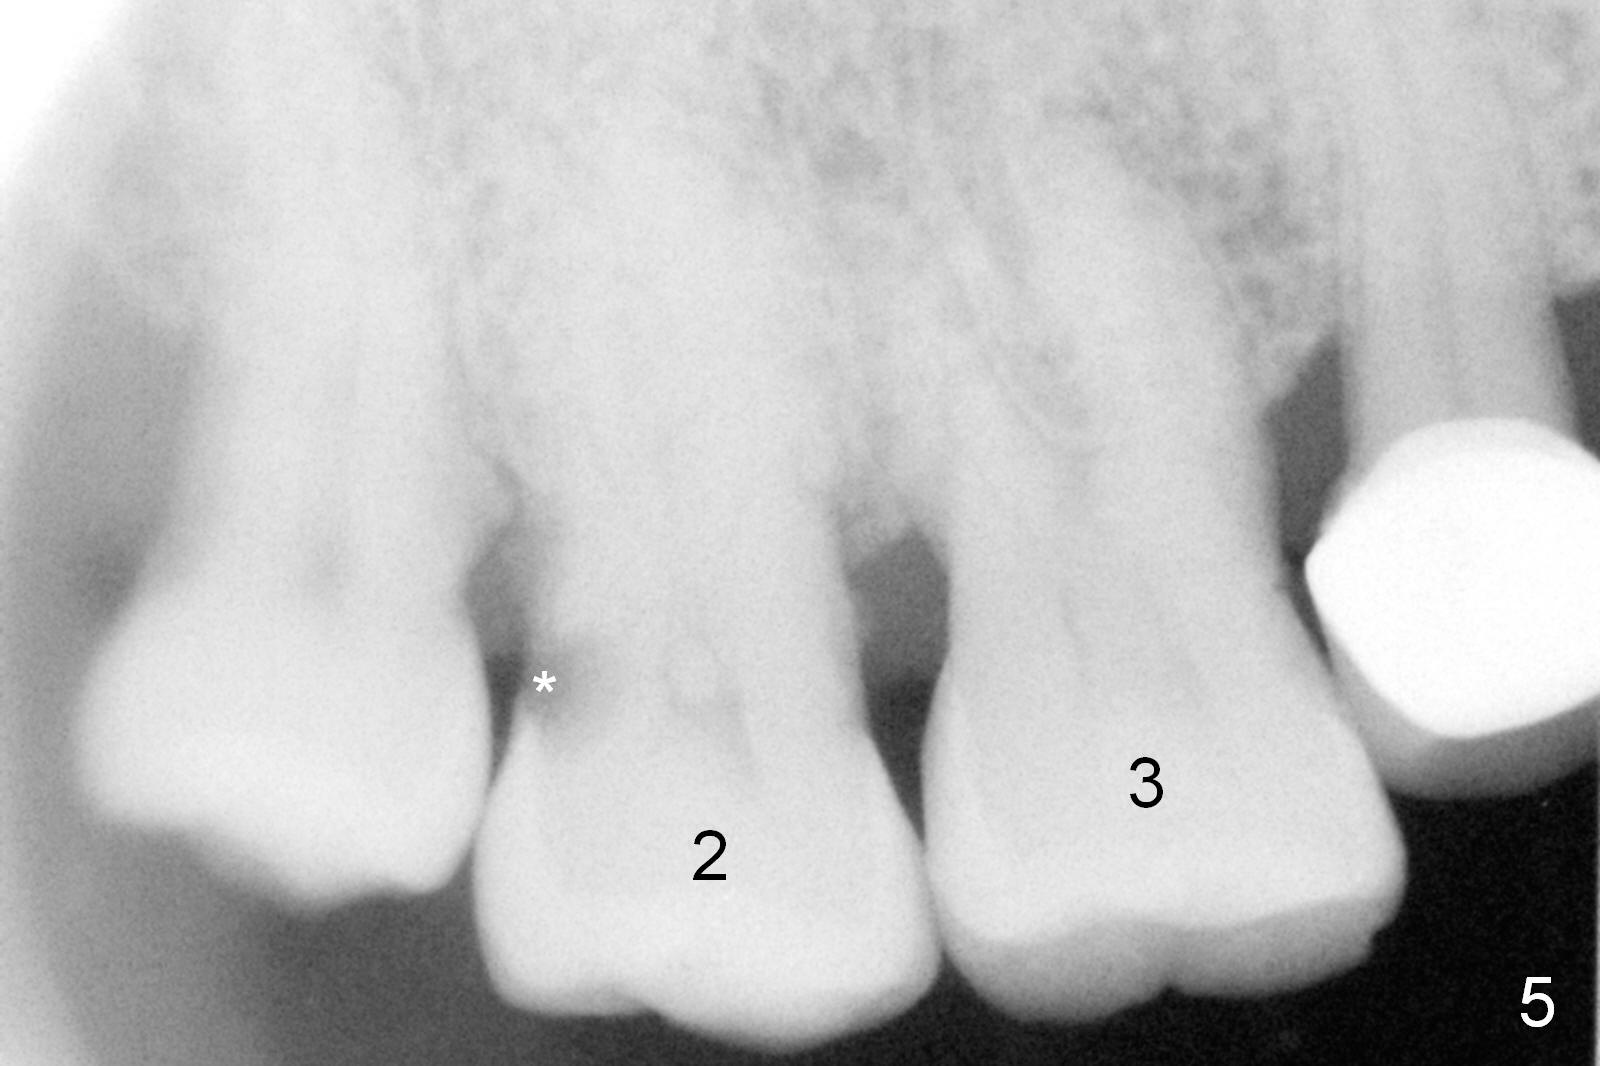

Re-examination clinically and radiologically reveals that there is no caries involving the tooth #3 (Fig.5). It appears that CBCT may have artifact. Treatment planning for intrusion should be modified. Mini-implants will be employed after #2 DO composite. Prepare Anchor mini-implant kit, 2 of 10 mm and 1 of 8 mm mini-implants, anesthetics and #15 scalpel. Scaling & root planing will be performed.